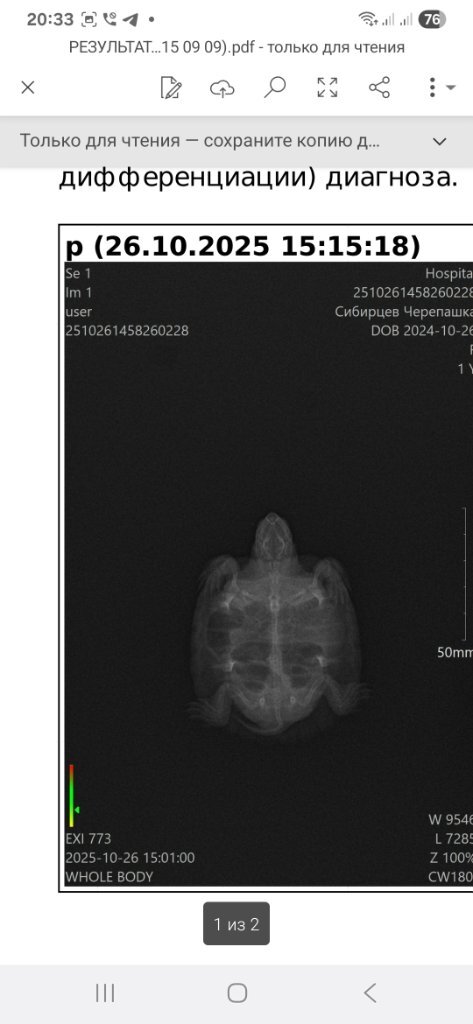

Тульская область.Тула , имя Евгений , мой возраст 42...владею недавно(3недели)красноухой черепашкой...ей уже год и 2 месяца, её вес был 52грамма , сейчас 46 грамм...попала ко мне с опухшими глазами и ничего не ела, глаза пролечили, открыла глаза и сразу налупилась 3 улитки, ракушки я не стал скармливать, тоьько тельце улиток, гусеницы шт. 2 , гамаруса...на следующий день сьела кусок щуки....теперь у нее темпия ...вздутие , плавает на поверхности и не может нырнуть....год черерашка жила в 50 литровке , воды примерно 15 литров, сейчас переселил в 200литровку , воды оде то 90 литров...камни лава под выход на обогрев , в террариум замущены улитки и надводные растения пистич и ряска....освещается камень лампой 2в1 с озона....скоро пииедет уф лампа...встановлен внутренний фильтр , обогреватель, старый не раблтал долго ,видимо,....спираль нерегорела когда то....что настораживает, так это то, что черепаха ничего не ест и теряет в весе...сейчас 46 грамм , было 52....прилогаю фото гентгена и фото нового места обитания